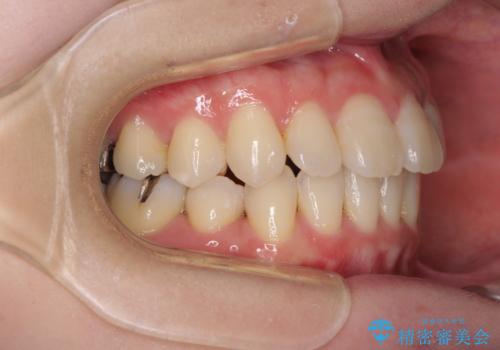

- 下顎の歯が舌側に倒れていることと、前歯の咬み合わせの不具合を気にして来院された患者様です。

受け口傾向の口元であるため、下顎左右小臼歯各1歯を抜歯して歯列を整えることとしました。

前歯には治療中の仮歯が装着されていたため、矯正治療後にオールセラミッククラウンにて補綴治療を行うこととしました。